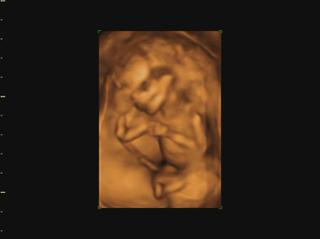

už som objednaná aj na 3D do KE... konečne môžem kľudne spávať 😀 😀 😀

@veronika1417 medzi 3d a 4d nie je skoro žiadny rozdiel, takže všade kde robia 3d robia aj 4d, lebo to štvrte D znamena čas,4d-real time, že mimi vidiš v realnom čase ako sa hybe.čiže stale je to 3d-trojdimenzionalne videnie babatka v 4d-realnom čase 😉

@luci66 juuuj Ty mas ake super informacie 🙂 to som vobec nevedela ze sa meria nosova kosticka a sijove prejasnenie, ten doktor na sone je taky dilino cely cas je ticho len tam znudene sedi a mna ide slaktrafit a trpnem ci je vsetko v poriadku ☹ ja som si veru sono uzila velakrat lebo sme dost lezali v nemocnici ale uz je to oki. Teraz uvidim miminko az 30.6 co je strasne daleko ☹ to uz budeme v 20 tyzdni 🙂 takze aj obrazok by mal byt uz kraaasny 🙂 mozno si dam aj ten 3D viem ze v Ba robia aj 4D ale v NR len 3D